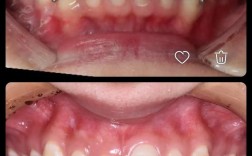

矫正牙齿是改善口腔功能和美观的常见方式,但不少人在矫正过程中或结束后发现牙齿有变黄的趋势,这确实让人困扰,牙齿变黄并非矫正的直接“副作用”,而是与矫正过程中的多种因素相关,本文将从原因、预防、处理等方面详细解析这一问题,帮助大家科学应对,矫...